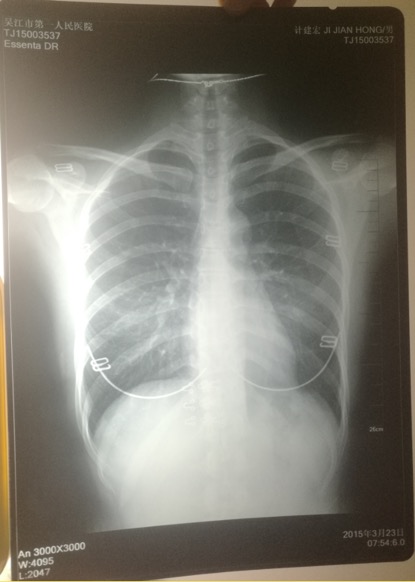

印有计建宏姓名的胸片实为一名女性的。 受访者供图

印着父亲姓名的胸片,图像却显示有明显女性文胸搭扣和项链的印记。

“当时我和母亲都奇怪,一年多前体检正常,怎么这么快肿瘤长得如此大了?”更令计云强疑惑的是,该院胸外科主任在系统中输入计建宏姓名后,查询得到的胸片,可明显看出有女性文胸的搭扣和项链,“后来医生含糊地说可能是同名同姓,便不让我看了。”

“7月初,我们回到吴江,带着满心悲伤和疑虑去了体检科,想搞清楚父亲的胸片究竟是怎么回事。”计云强称,此后几经周折,在找了吴江区第一人民医院体检科、投诉科等多个部门后,耗时多月,才被体检科通知去拿父亲的胸片,“一张是我父亲的名字,但有文胸印记;另一张是医院所谓的我父亲的胸片,显示的是其他人的姓名。”